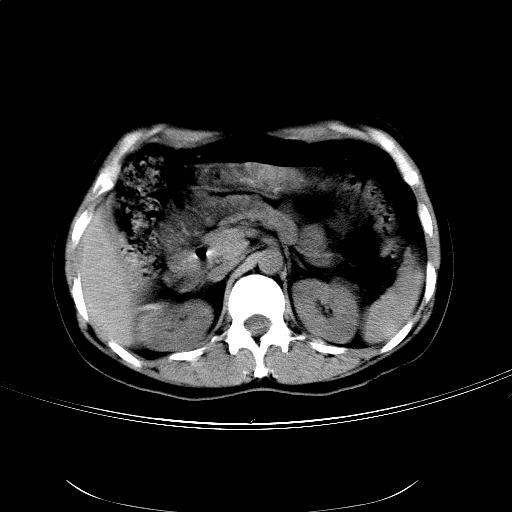

女,36岁,右上腹不适数天。5天后公布结果。

肝左叶有俩原形低密度,边缘光整,内密度均匀一致,考虑小囊肿。

右侧肾上腺区域不规则低密度占位性病变,似乎有俩病灶不完全相连。密度不均匀,内见钙化。首先考虑囊肿,建议增强薄层扫描。

支持1肝内小低密度灶考虑多系囊肿。2右侧肾上腺区低密度结节影,其内见两个小点状钙化灶,低密度影似有分叶或为两个,右肾上部显示不清。考虑右侧肾上腺良性占位病变,请结合临床及超声与增强检查。

比较典型的右侧肾上腺囊肿;肝脏左外叶上段小囊肿。

结果:肾上腺囊肿。